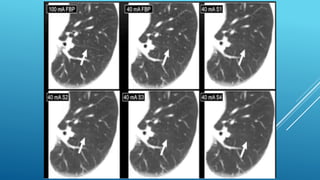

FBP ADVANTAGES

 Speed : 50 – 60 + images recon

per second.

 Well characterized:

 Primary recon since beginning of

CT.

 Noise properties known: linear

relationship between noise and

resolution

 Known Artifacts

ITERATIVE IMAGE

RECONSTRUCTION(IRT)

Incorporates better mathematical CT model and iterates to

reduce inconsistencies in the image reconstruction.

Lower noise and artifacts at low dose.

Generally slower than FBP.